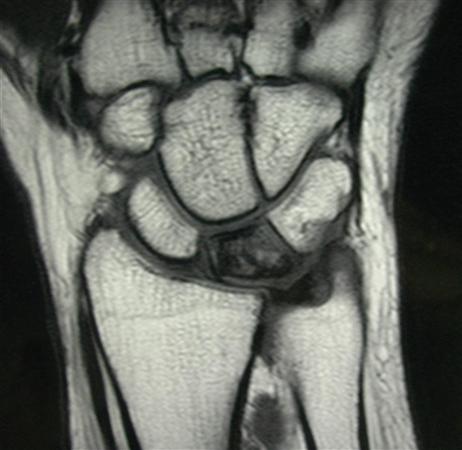

육체노동을 많이하는 남자에서 생기는 질환입니다. ulnar impaction syndrome 과는 반대로 ulna variance가 음성인 경우가 많으며

정맥 관류 차단에 의한 골내압력증가로 인하여 괴사가 진행된다고 추측하고 있는 질병입니다.

증상으로는 파악력이 감소되며 수근 관절 굴곡 제한이 많이 있습니다.